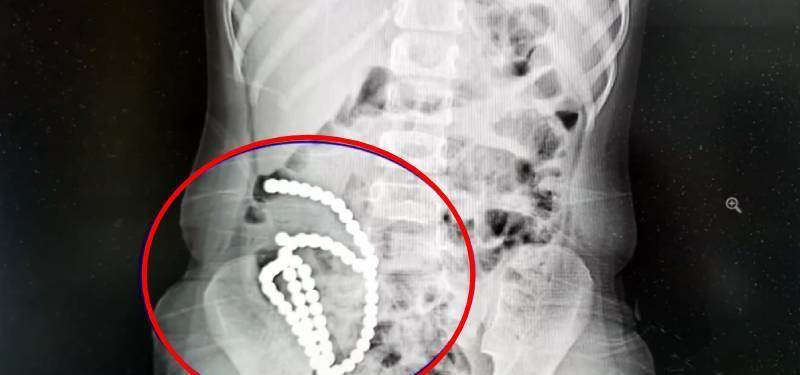

家有幼兒一定要特別小心照顧,如有不慎恐怕後悔一輩子也來不及。中國浙江大學醫學院附屬兒童醫院的急診來了一位小病患,4歲小妹妹肚子痛一個月以為是腸胃炎,直到轉院檢查照X光才發現「肚子裡有一串珠珠」。雖然緊急開刀治療,未來罹患後遺癥的風險卻相當高。

根據中媒《人民網》報導,院方發現4歲女童肚子裡有像手飾一般的串珠後,懷疑是誤吞磁力很強的「巴克球」磁力珠。問診後女童媽媽也透露家裡有這種玩具,平常是孩子的哥哥在玩。

經過將近2小時的手術,醫師將多達61顆磁力珠從女童的腸胃裡取出。

副院長兼腔鏡中心主任高志剛醫師表示,女童並非一下子把磁力珠通通吞下肚,而是分次慢慢誤食。前後吞下去的珠子因為磁力相吸,「2顆巴克球之間就會有腸管壁夾在中間,慢慢腸子就穿孔了」。高醫師說明把磁力珠取出後,女童的腸壁破了14個洞,雖然手術成功修補,但仍對健康造成極大的損害,「一輩子腸沾黏、腸梗阻的風險都很大」。